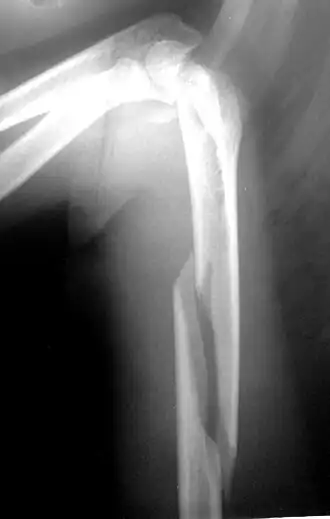

Рентгенограмма при многооскольчатом переломе плечевой кости в нижних отделах. Возможны внесуставные и внутрисуставные переломы плеча в нижних отделах. К внесуставным переломам нижних отделов плеча относятся надмыщелковые переломы, к внутрисуставным переломам — переломы блока, головчатого возвышения плечевой кости и межмыщелковые переломы.

надмыщелковые переломы

С учётом механизма травмы Надмыщелковые переломы плеча подразделяются на разгибательные и сгибательные. Сгибательные надмыщелковые переломы встречаются чаще, возникают при падении на согнутую руку. Причиной разгибательного перелома становится падение на переразогнутую руку.

- Симптомы

Область плеча над локтевым суставом отечна, резко болезненна. Сгибательные переломы сопровождаются визуальным удлинением предплечья, при разгибательных переломах предплечье выглядит укороченным. Надмыщелковые переломы плеча могут сочетаться с вывихом костей предплечья. Диагноз устанавливается после рентгенографии.

- Лечение

При неосложненных переломах область повреждения фиксируют гипсовой лонгетой на 3-4 недели. При большом смещении отломков и невозможности репозиции выполняют операцию.